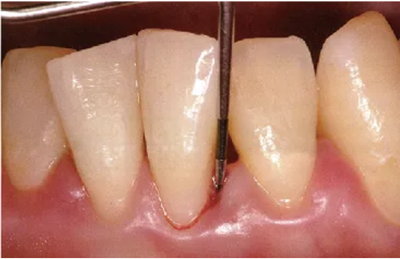

頰側(cè)、舌側(cè)的測(cè)定

探針要與牙軸平行插入。注意不要探針的尖端離開牙面。

舌側(cè)數(shù)值難以讀取,要學(xué)會(huì)利用口鏡來讀取。

● 頰側(cè)、舌側(cè)探針的插入

通常與牙軸平行插入

舌側(cè)難以看到的位置就利用好口鏡來輔助。

注意盡量讓探針貼著牙面。